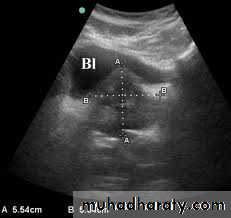

PROSTATIC Enlargement

Common cause of lower urinary obstruction . Either Benign prostatic hyperplasia or Carcinoma .Benign Hyperplasia :-

• IVU ( cystogram stage )

• * Elevated bladder base .• *Lower ureter elevated and curved (fish hook ).

• * Back pressure to both kidney & ureters .

• * Thick trabeculated bladder wall and diverticula formation .

• * Large size prostate produce filling defect like appearance .

• * Post-voiding residual volume .